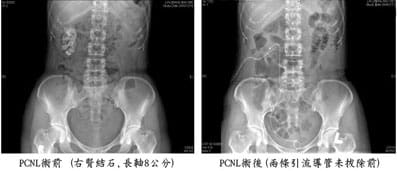

尿路結石的處理方法有許多種,包括現在普遍使用的體外震波碎石術(ESWL)、內視鏡手術及傳統開刀手術。對於巨大的腎結石或腎盂輸尿管交接處的結石,單用體外震波碎石術,往往無法一次完全擊碎,並且擊碎後常引起碎小結石阻塞輸尿管使病情愈趨複雜,這種情況最適合進行經皮腎造瘻截石手術(PCNL)

,將大部分的結石直接取出,若有殘餘結石,再配合體外震波碎石術,才可以獲得最好的效果。雖然與PCNL同時發展的體外震波碎石術在1984年後已大幅降低PCNL的臨床應用,PCNL在治療尿路結石上仍有其無可取代的地位,是治療尿路結石的重要方法。

這種平躺姿勢的手術方式於1990年首度由Valdivia報告,1998年報告累積557例、採用X光透視定位的手術成績,其手術效果良好,併發症的機率沒有增加,並且沒有一般醫師所擔心的腸穿孔併發症。以往採用趴臥姿勢,一大理由即根源於此,擔心平躺姿勢較有腸穿孔的危險;反而是曾有二篇醫學報告分別提出四百例及一千例趴臥姿態的手術成績,各有一例及二例大腸穿孔的併發症。我們自1998年12月即改採用平躺姿勢,結合超音波定位技術,至2003年12月累積完成315例手術,腎結石有294例(93.3%),大的阻塞性上端輸尿管結石有21例(6.7%)。其中178位男性(60.3%)、117位女性(39.7%),共295位病患,年齡從26到88歲,平均52.6歲。右側結石142例 (45.1%),左側結石173例 (54.9%);需進行第二次PCNL的有6位男性、14位女性,共20位病患(6.8%)。結石大小從 35到3603 mm2不等, 平均660 mm2。手術時間由65到290分鐘,平均156分鐘;結石廓清率0-100%不等,平均82%。有4例(1.3%)因腎臟通道消失不見而手術失敗。失血量 50到1000 ml,平均225 ml;有61例(19.4%)需輸血PRBC 2-4單位。45位高危險群病患,術後沒有因心肺血管併發症需住加護病房照顧;沒有重大併發症包括動靜脈瘻管或失血過多需要接受動脈栓塞或開刀手術止血;同時也沒有腸穿孔、氣胸或水胸等其它重大併發症。